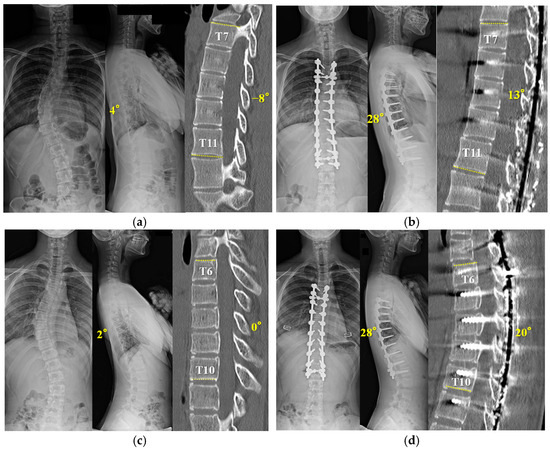

A fifteen-year-old girl with Lenke 1A- was used as the representative case (Figure 5a,b). (a) A preoperative X-ray showed thoracic hypokyphosis of 4°. Apical five vertebral kyphosis was −8 degrees. (b) She underwent T4-L2 posterior spinal fusion surgery with concave RR and convex DRC using the outrigger. After the apical setscrews were tightened (T7–11), segmental DVR for thoracolumbar curve-correction was performed from T11 to the lowest instrumented vertebra (L2). After surgery, TK increased to 28°. Next, a thirteen-year-old girl with Lenke 1B- was shown (Figure 5c,d). A preoperative X-ray showed thoracic hypokyphosis of 2°. She was found to have six non-rib-bearing vertebrae (L1–6). Apical five vertebral kyphosis was 0 degrees. (b) She underwent T5-L2 posterior spinal fusion surgery with concave RR and convex DRC using the outrigger. After the apical setscrews were tightened (T6–10), segmental DVR for thoracolumbar curve correction was performed from the caudal neutral vertebra (T12) to the lowest instrumented vertebra (L2). After surgery, TK was increased to 28°.

The X-ray and CT show a fifteen-year-old girl with Lenke 1A- scoliosis (a,b), and a thirteen-year-old girl with Lenke 1B- (c,d). (a) Preoperative X-ray shows a Cobb angle of 48° and 4° of TK. Apical five vertebral kyphosis is −8 degrees. (b) Postoperative X-ray shows a Cobb angle of 5°and 28° of TK after posterior fusion and correction using the outrigger. Apical five vertebral kyphosis is improved by 13 degrees. (c) Preoperative X-ray shows a Cobb angle of 51° and 2° of TK. Apical five vertebral kyphosis is 0 degrees. (d) Postoperative X-ray shows a Cobb angle of 5°and 28° of TK after posterior fusion and correction using the outrigger. Apical five vertebral kyphosis is improved by 20 degrees.